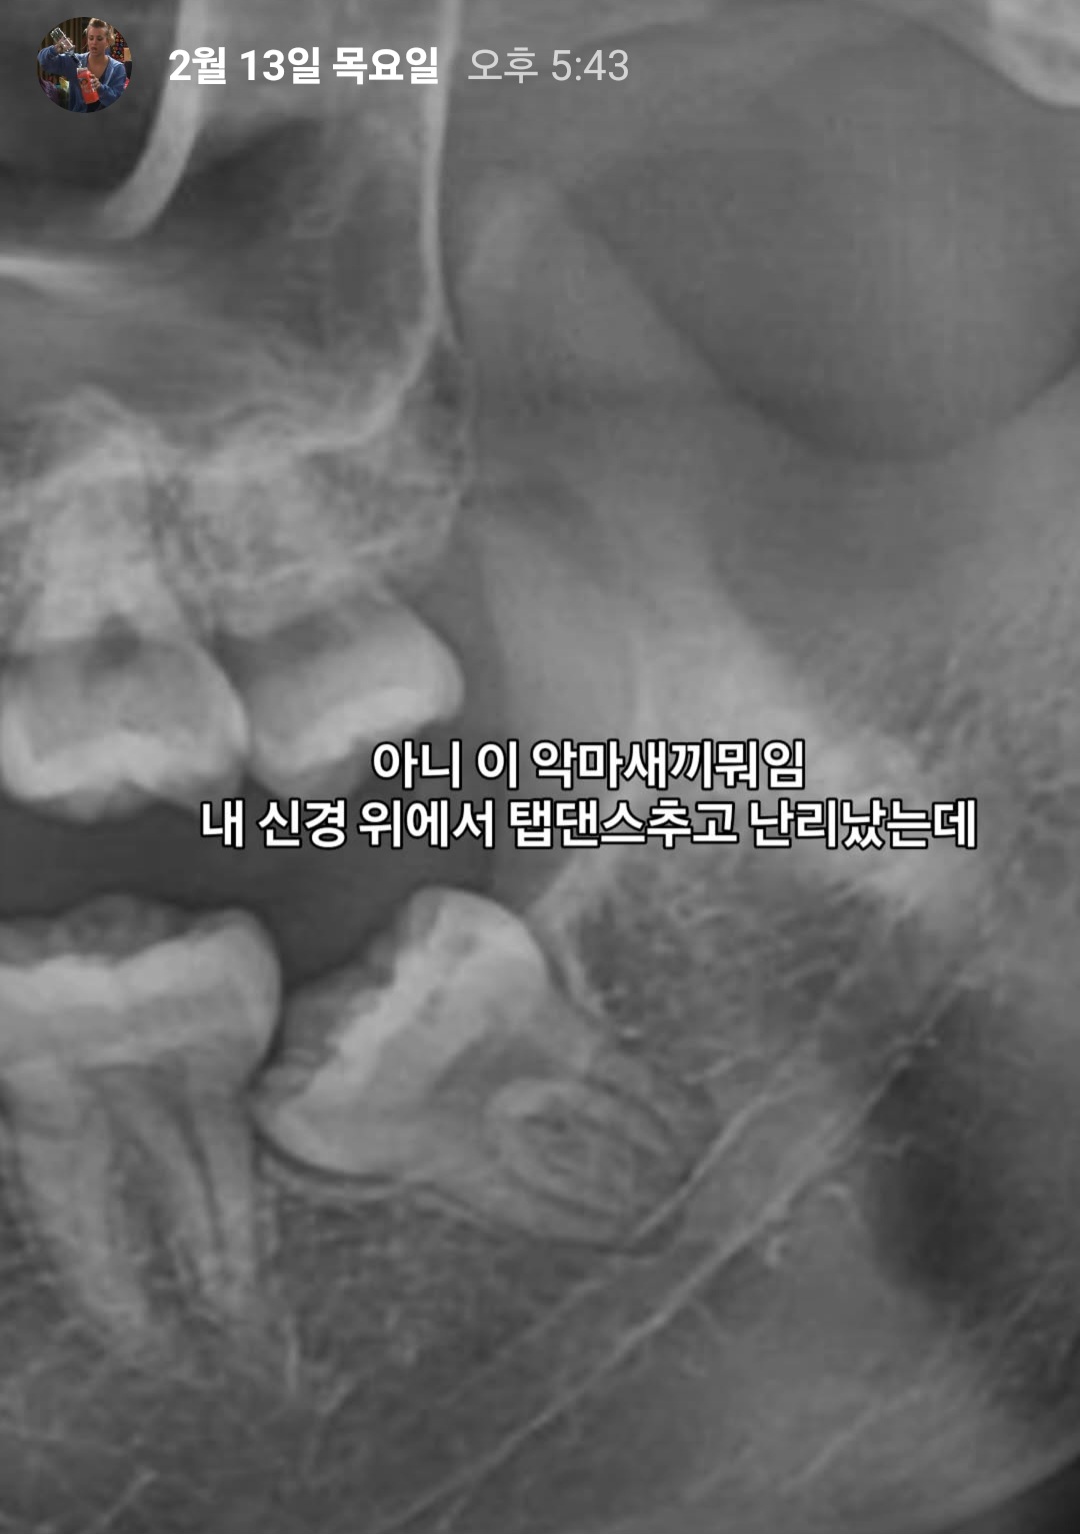

그리고 내 안의 악마를 죽이는 날

(사랑니 뽑으러 왔단 소리)

썰을 좀 풀자면 일단 얘가 구라가 아니라

제 신경에서 탭댄스를 추거든요?

그래서 딱히 아프진 않았는데 이대로 가다간

내 어금니를 얘가 끌어안고 자살하실 각이라 감

당근 의사쌤도 음 안뽑으면 좃대실 사랑니구요

이래서 바로 약속 잡고 뽑았음